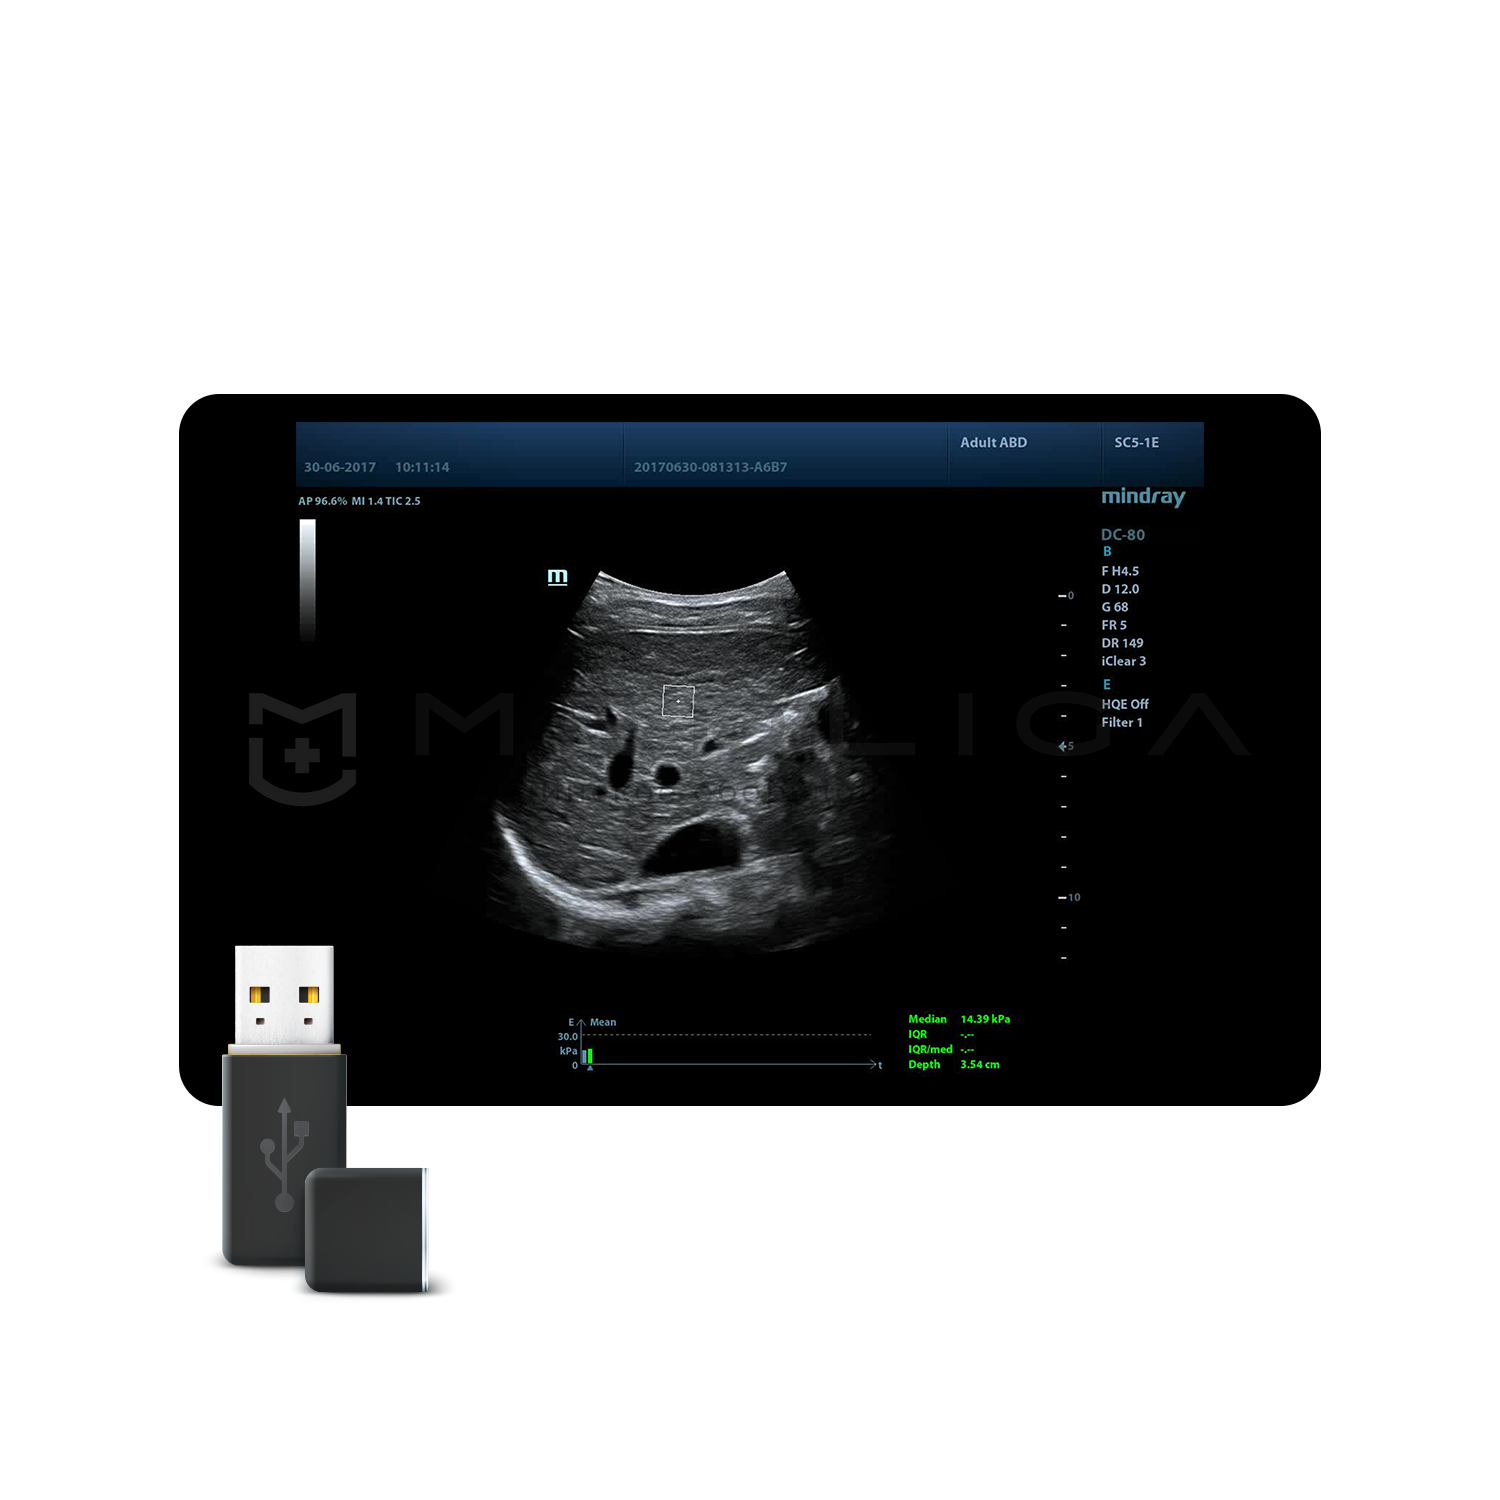

STQ (Sound Touch Quantification)

Sound Touch Quantification (STQ) позволяет быстро в режиме реального времени оценить жесткость ткани печени и определить стадию фиброза.